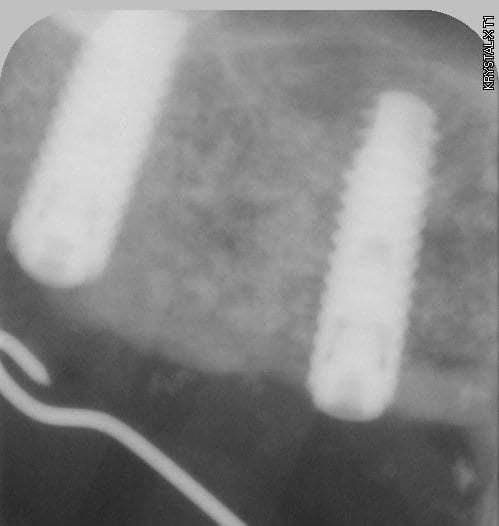

ici c'est un mix (pour un impératif perso): en 25 un easy-implant master s puis 2 dentium superline.

Le easy c'est du sablé au corindon et les dentium sablés-mordancés SLA http://www.dentogem.com/viewpage.php?pageid=48

j'ai donc procédé à la mise en fonction ce matin, 7 mois après l'intervention. Mise en place de piliers de cicatrisation assez hautes et surtout de diamètres en adéquation avec une PM et 2M. je prends l'empreinte dans 3 semaines , la gencive sera belle autour des piliers.